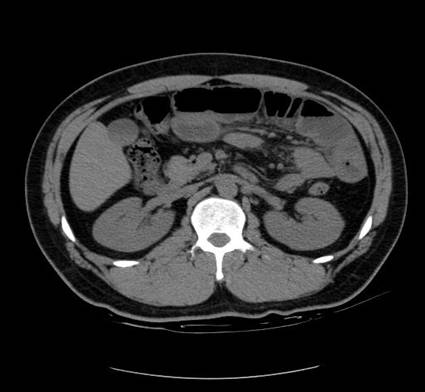

以下是引用zsl6918在2007-6-22 21:08:00的发言:[br]病史较长,反复发作,基本排除恶性病变,腹部定位像可见是小肠梗阻征象,原因无非是肠源性,血管性和神经性的,肠源性的在排除占位后应想到 肠旋转不良的可能,血管性的应想到肠系膜血管的栓塞,神经性的要想到植物神经功能紊乱的可能,本病例应该强化检查帮助诊断,个人感觉旋转不良可能性大。

以下是引用青莲居士在2007-6-24 12:27:00的发言:[br]肠梗阻[br]肝内胆管结石